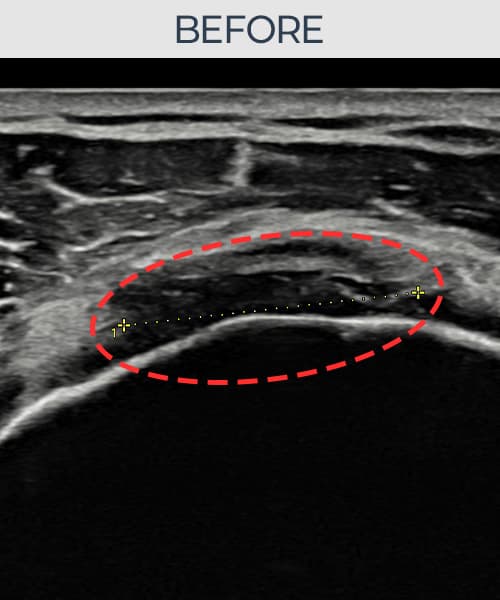

시술 전 초음파 측정 결과 파열 크기는 8mm × 5mm (힘줄 두께의 약 45% 결손)로 확인되었습니다. 시술 전 초음파에서 관절면측 회전근개 부착부의 두께 감소와 힘줄-뼈 접합부의 에코 불균질성이 뚜렷하게 관찰되었습니다. 시술 후 초음파에서 부착부 두께가 유의하게 증가하였고, 힘줄 내부의 에코 패턴이 균질하게 회복되었습니다.

40대 중반 여성 환자분으로, 두 아이를 키우며 집안일을 혼자 도맡아 하시는 분이었습니다. 빨래 널기, 높은 곳 정리 등 팔을 위로 올리는 동작에서 통증이 반복되다 점차 일상적인 동작에서도 통증이 생겨 내원하셨습니다. 초음파 검사에서 관절면측 회전근개 부착부의 두께 감소와 부분파열이 확인되었으며, 비수술 축소봉합술로 인대-뼈 부착부를 고정하는 치료 계획을 수립하였습니다. 시술은 30여 분 만에 완료되었고 당일 귀가하셨으며, 시술 후 2주째부터 가벼운 생활 동작을 단계적으로 허용하였습니다. 6주 후 추적 초음파에서 봉합 위치가 안정적으로 유지됨을 확인하였고, 최종 경과 관찰에서 부착부 두께가 유의하게 증가하여 통증 없이 가사 활동이 가능해지셨습니다.